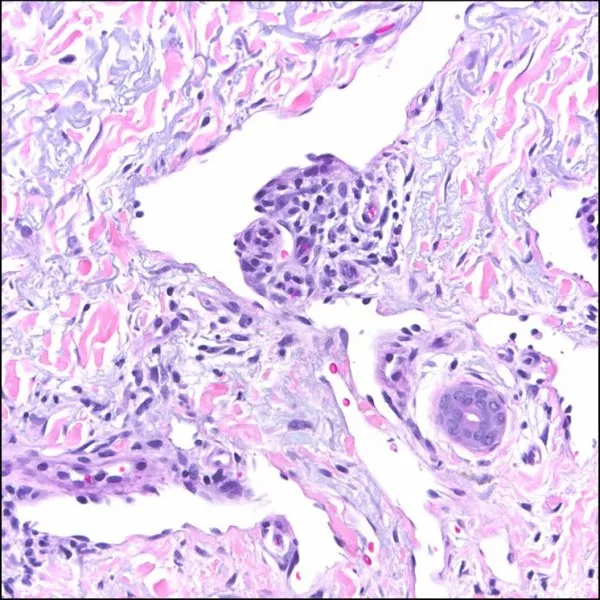

Profilaktyka HIV, na zdjęciu widać mikroglej po kontakcie z wirusem HIV. Obraz wskazuje na encefalopatię powodowaną przez HIV.

Ryc. A – pewnie nie widać, ale jest to tkanka nerwowa, która nie jest do końca prawidłowa. W jej obrębie widać mikroglej, który w następstwie kontaktu z wirusem HIV uległ przemianie do wielojądrzastej komórki mikrogleju. Taki obraz jest typowy dla encefalopatii powodowanej przez HIV. Mikroglej to komórki pochodzące z mezodermy, a ich funkcja w ośrodkowym układzie nerwowym jest analogiczna do funkcji leukocytów. Jest to wyjątkowa populacja komórek na obszarze OUN, gdyż jako jedyny element tkanki nerwowej nie pochodzi z neuroepitelium.